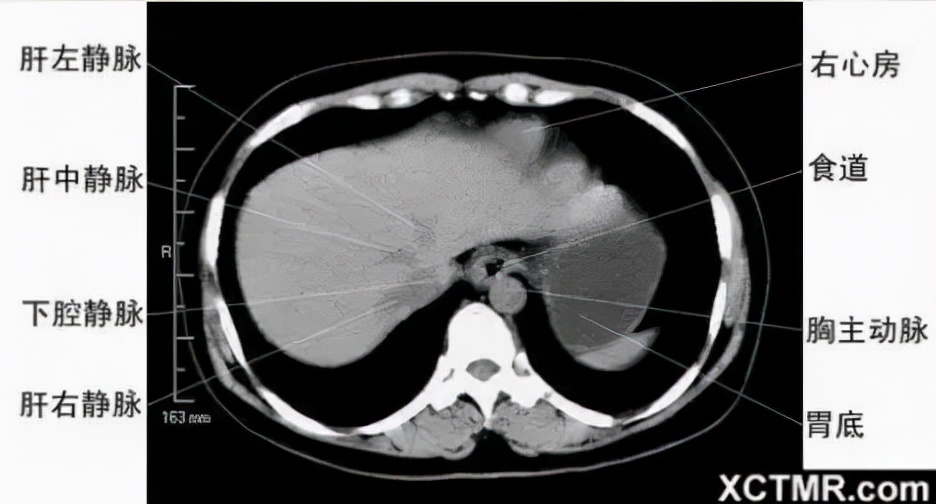

腹部CT